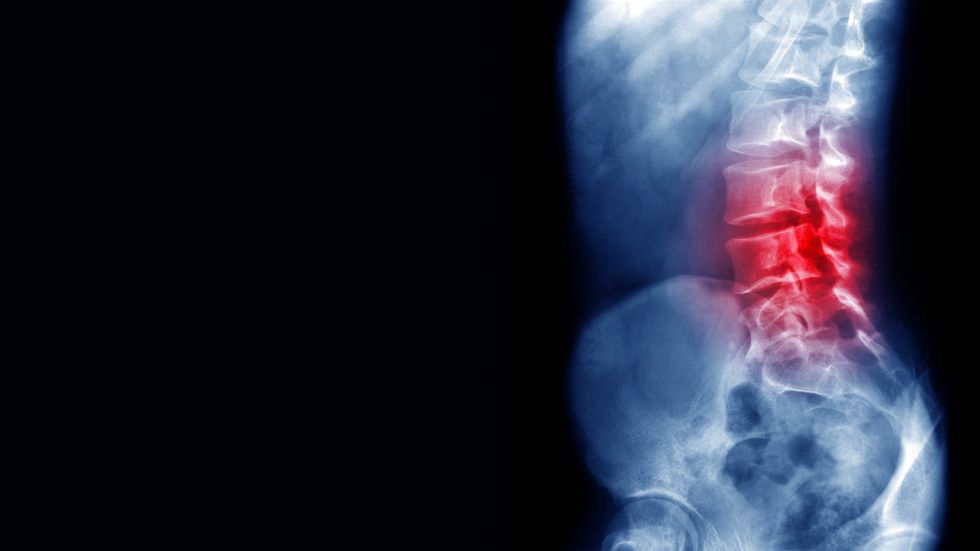

With osteoporosis affecting millions globally and often resulting in debilitating fractures, the search for food-derived bioactive compounds has intensified.

Osteoporosis affects millions globally